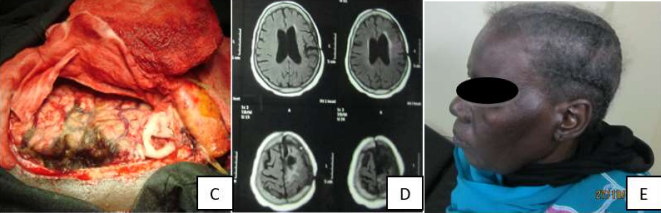

Fifty years old female worker, presented complaining of pain in the left eye and ear, sensation of collapse, fatigue, vertigo and headache for the last one year which was progressive in nature.

On examination she looked well, conscious and oriented, had only mild weakness of the right upper extremity power grade 4. CT scan and MRI of the brain showed left frontal brain tumor with ventricular compression and midline shift.

CT scan (A) and MRI (B) of the brain showed left frontal brain tumor with ventricular compression and midline shift. Total surgical resection was done through left frontal craniotomy.

Histopathology revealed fibrous and meningiothelial meningioma.

Image (C) is an operative image after total resection of the tumor, Image (D) is post-operative MRI showing no evidence of a residual tumor, Image (E) is the patient after full recovery one year post-operative.